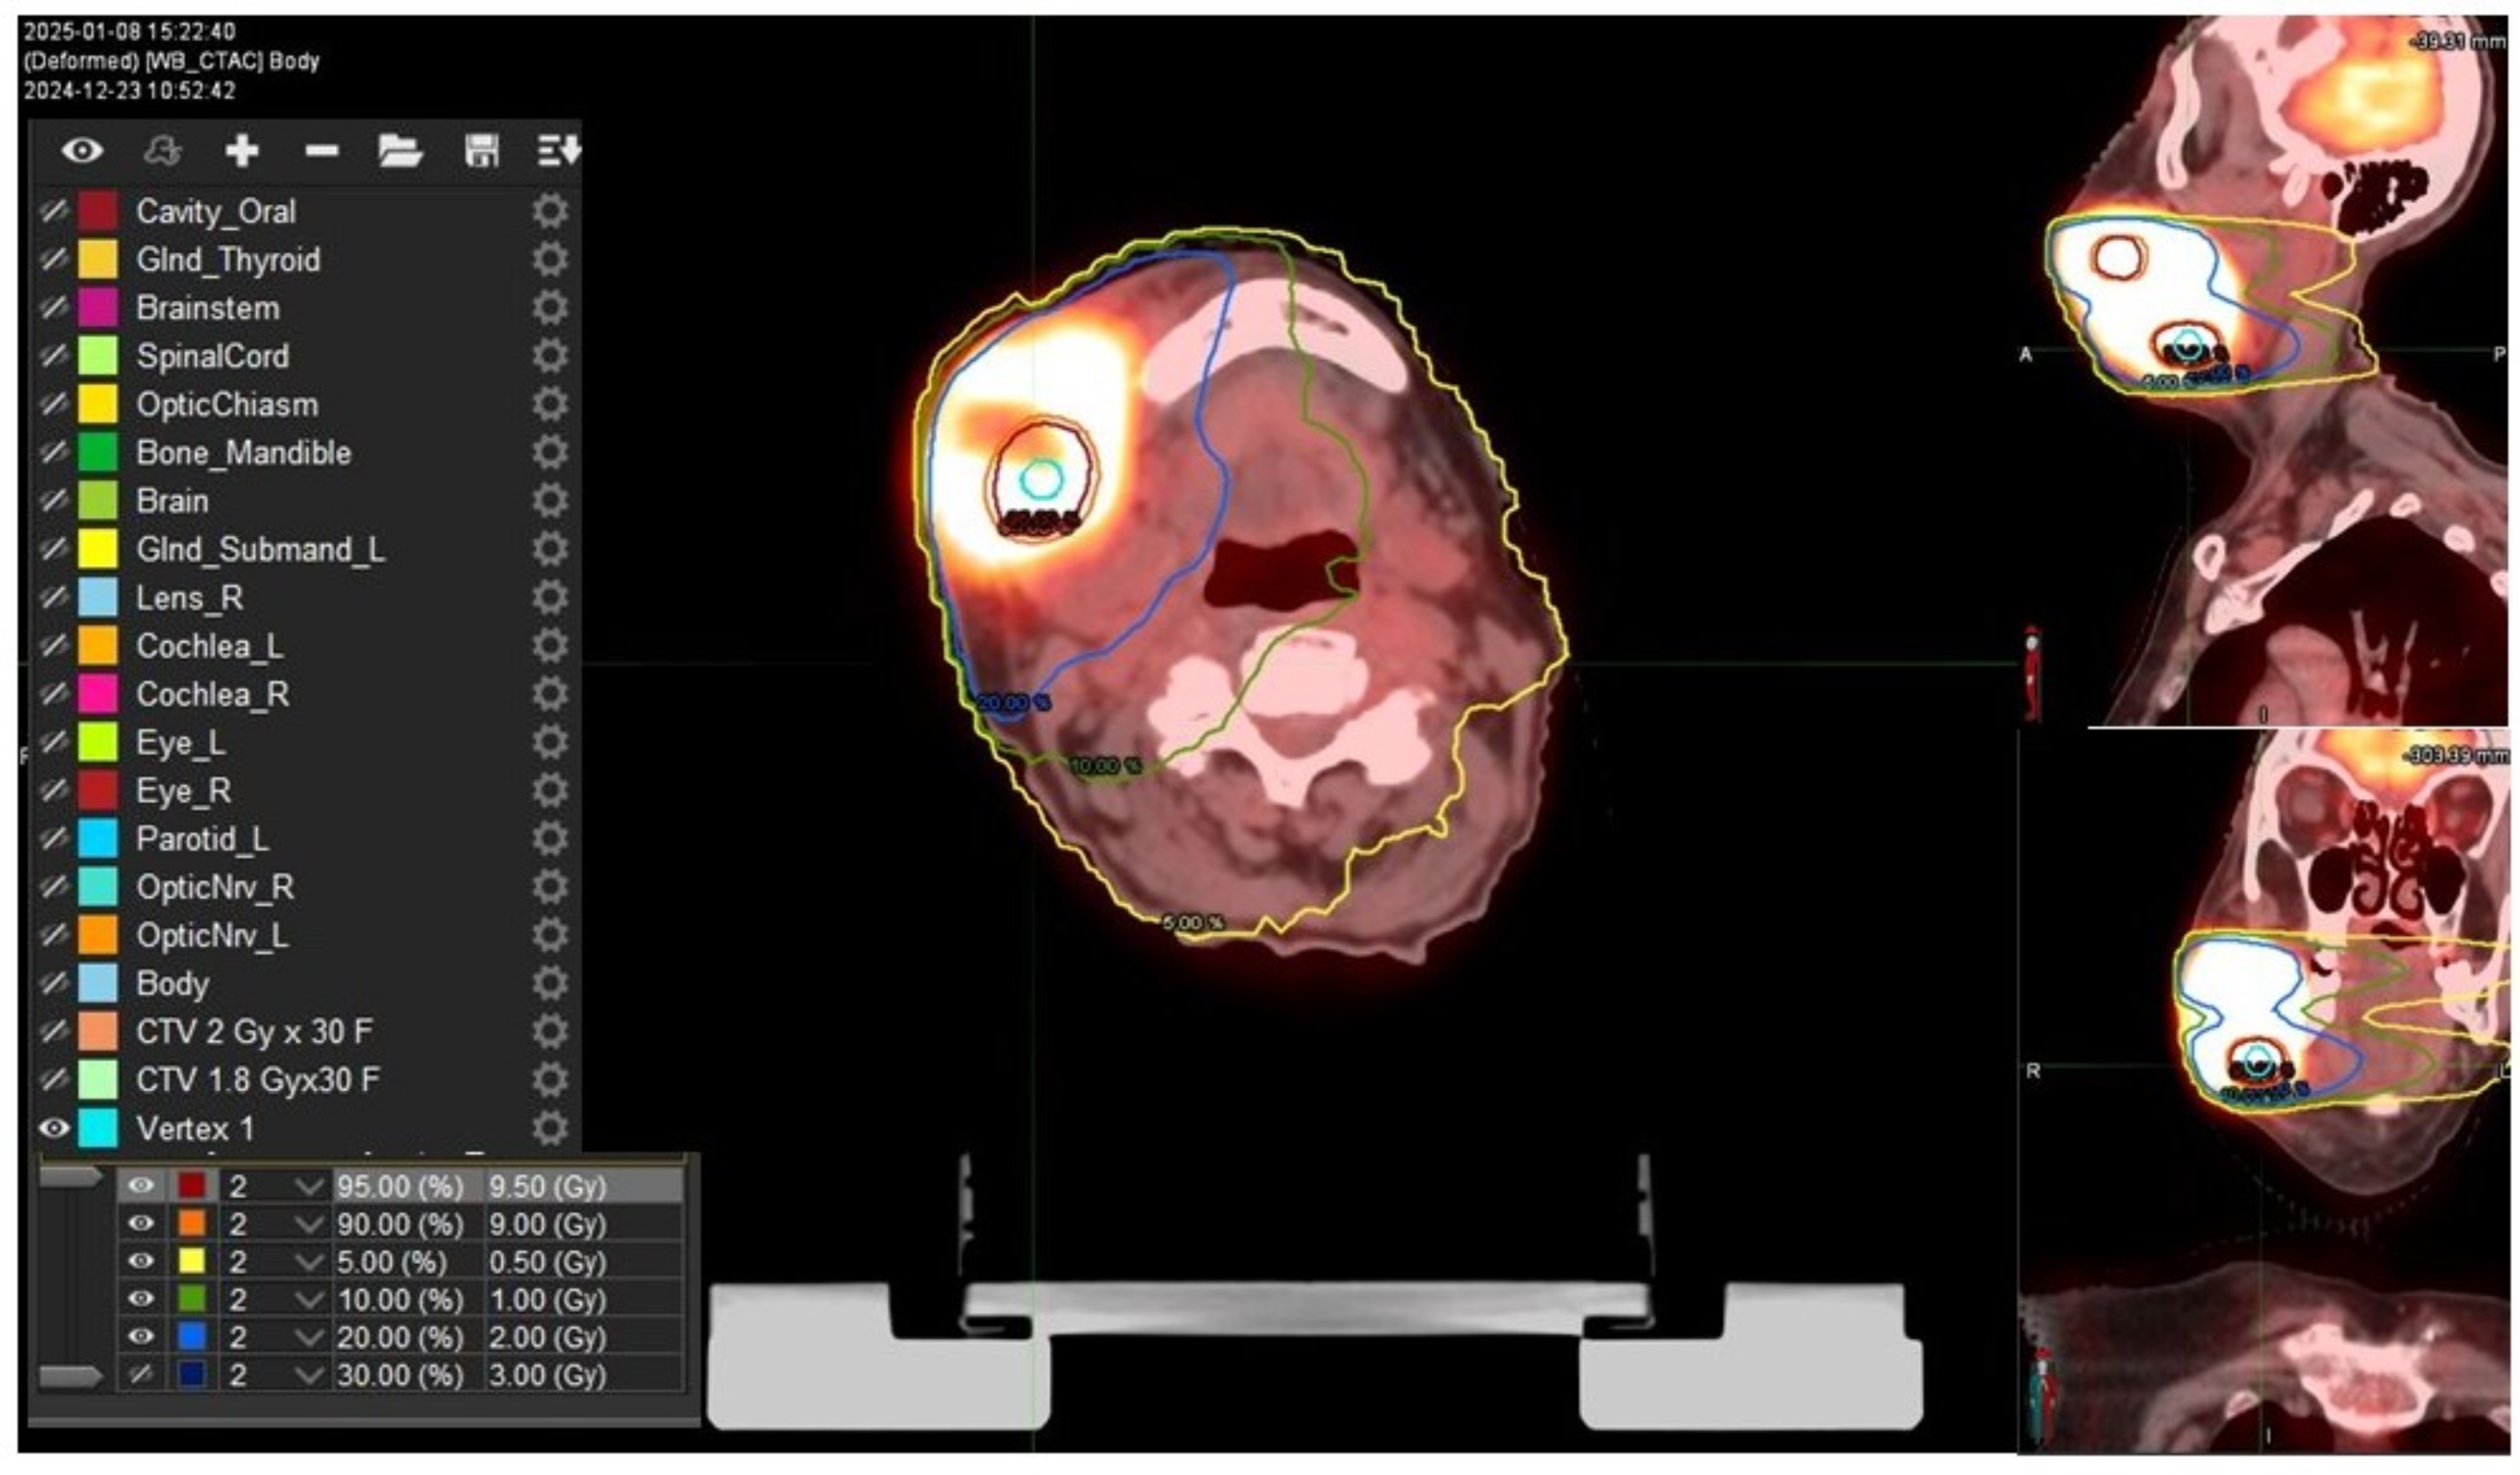

2. Case Presentation

3. Discussion